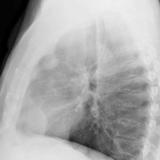

Case 9 Thymoma Lat

Date: 04/04/2010

Views: 3257